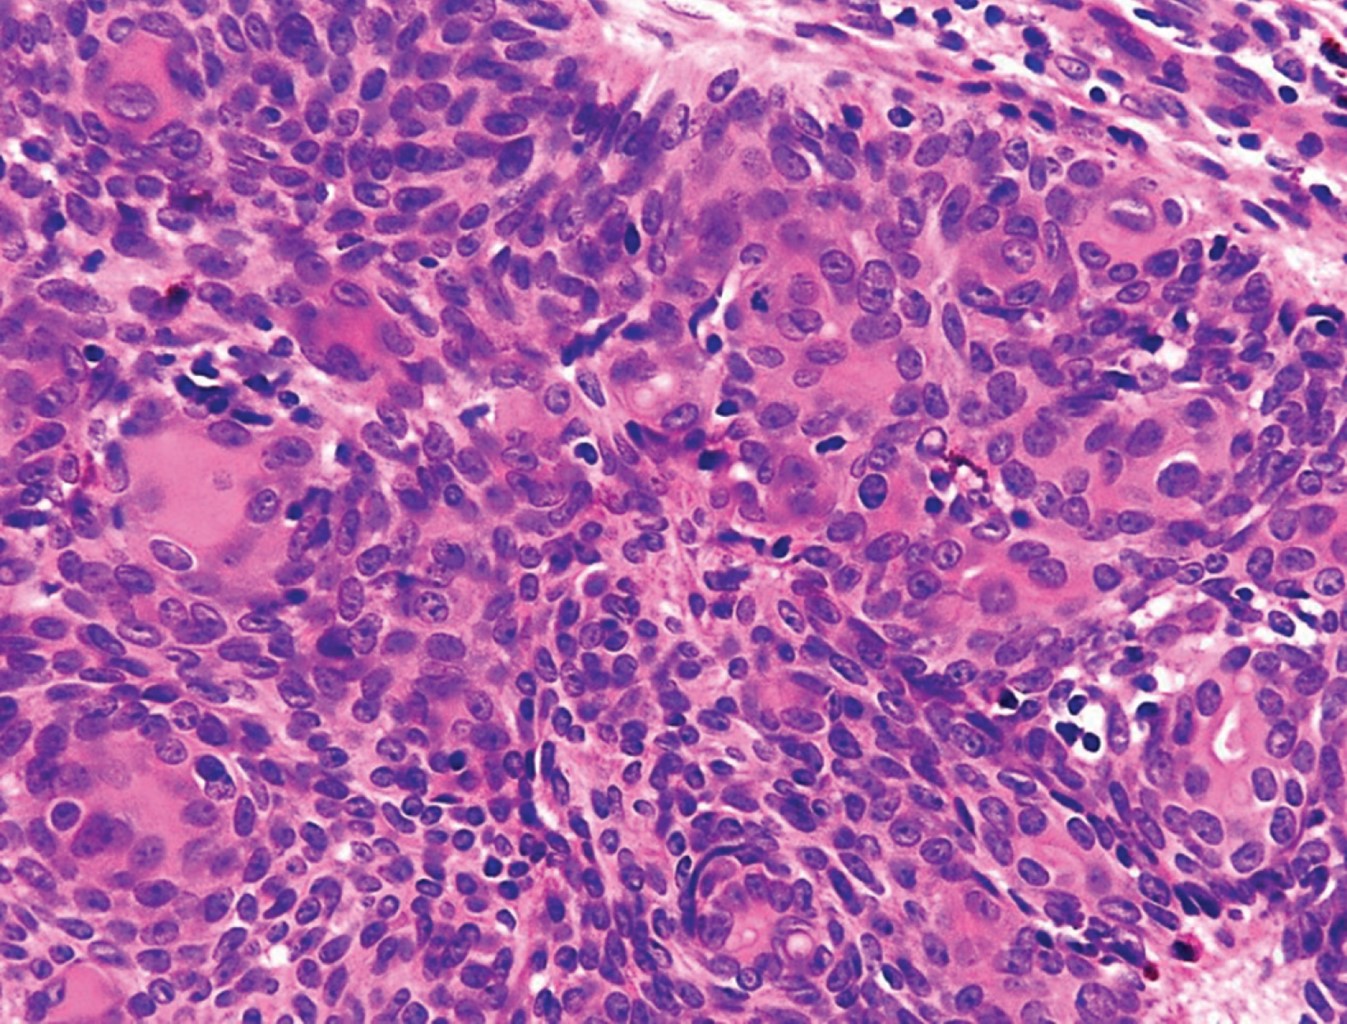

Con la sospecha clínica de probable poroma ecrino se realiza biopsia excisional. El estudio histopatológico reporta neoformación Exofítica, cuya epidermis muestra hiperqueratosis paraqueratósica (Figura 3). En todo el espesor de la dermis se observan cordones tumorales conectados con la epidermis, los cuales se anastomosan atrapando papilas (Figura 4); están constituidos por células de núcleos basofílicos, algunas de las cuales presentan núcleos grandes e hipercromáticos, mitosis anormales y metaplasia escamosa; presentan estructuras ductales y pigmento melánico, rodeados por una moderada reacción inflamatoria (Figuras 5 y 6). El diagnóstico histopatológico fue de porocarcinoma ecrino. En el Servicio de Dermatooncología de esta Unidad se efectúa extirpación quirúrgica más amplia, con margen de 7 cm, con reparación del defecto llevando a cabo un injerto, sin evidenciar lesión tumoral remanente en la histopatología. Al considerarse un tumor con alto potencial metastásico, se envía al paciente a hospital de tercer nivel para hacer estudios de extensión y seguimiento.

Figura 5

Figura 6